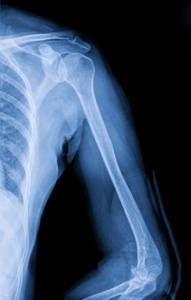

Больная Т., 48 лет, была доставлена в НИИ СП им. Н.В. Склифосовского после падения на улице. В приемном отделении диагностировали закрытый многооскольчатый внутрисуставной перелом правой плечевой кости в нижней трети со смещением отломков. Диагноз подтвержден спиральной компьютерной томографией с 3.0-реформацией (рис. 1). При оскольчатых диафизарных переломах мы предпочитаем в качестве фиксатора использовать интрамедуллярные блокируемые штифты различных конструкций, но в данной ситуации применить подобный вид фиксации было невозможно, т.к. перелом распространялся дистальнее костно-мозгового канала. Предположив, что во время открытой репозиции осколки будут «проваливаться» в костно-мозговой канал, мы решили, что будет проще сопоставить их на какой-то основе-каркасе.

Рис. 1. Оскольчатый внутрисуставной перелом плечевой кости в нижней трети со смещением (спиральная компьютерная томограмма — 3D-реформация)

После обнажения места перелома между дистальным и проксимальным отломками поместили трансплантат,на который уложили осколки, которые, по возможности, фиксировали винтами, а затем реконструктивной пластиной (рис. 2). Наличие трансплантата значительно упростило репозицию и позволило достаточно прочно фиксировать отломки. В послеоперационном периоде конечность фиксировали шарнирным ортезом. Движения в локтевом суставе разрешили через 5 нед после операции. При контрольной рентгенографии правой плечевой кости через 3,5 мес после операции выявлены четкие признаки образования костной мозоли (рис. 3). Амплитуда движений в локтевом суставе составила 0-5-100 градусов.

Рис. 2. Перелом после остеосинтеза реконструктивной пластиной (стрелкой указан трансплантат): а — прямая проекция

Рис. 3. Срастающийся перелом: а — прямая проекция, б —боковая проекция